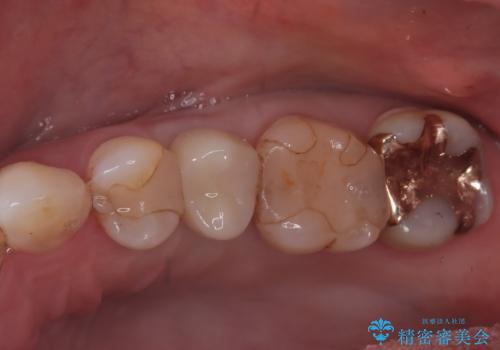

40代女性 奥歯のインプラント治療②~インプラントの埋入~

無くなってしまった奥歯のかみ合わせを回復するためのインプラント治療を希望されました。

抜歯後、治りを待ってからインプラントの埋入手術(1次手術)をおこないました。

骨の幅が一部薄くなっており、これを補填材+吸収性メンブレン(膜)で覆う形での術式となりました。